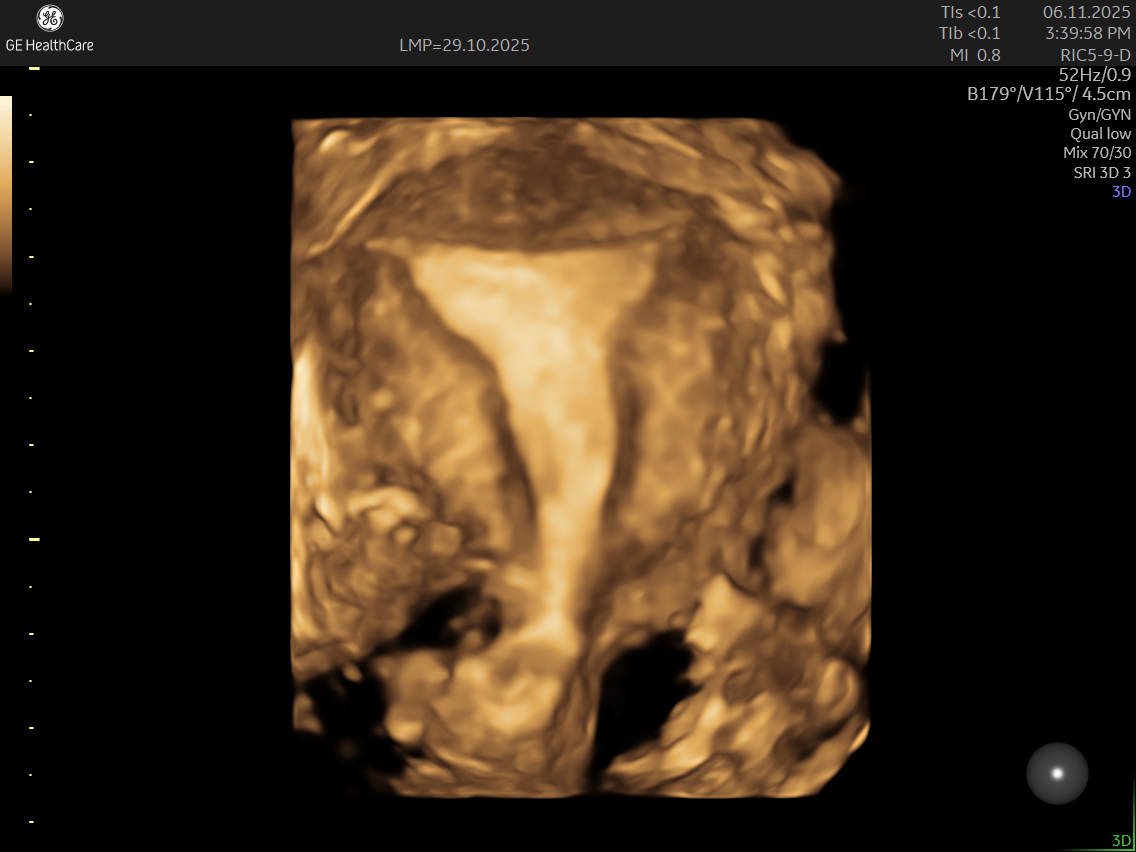

IMAGE GALLERY